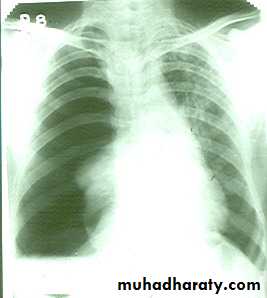

Massive pleural effusion